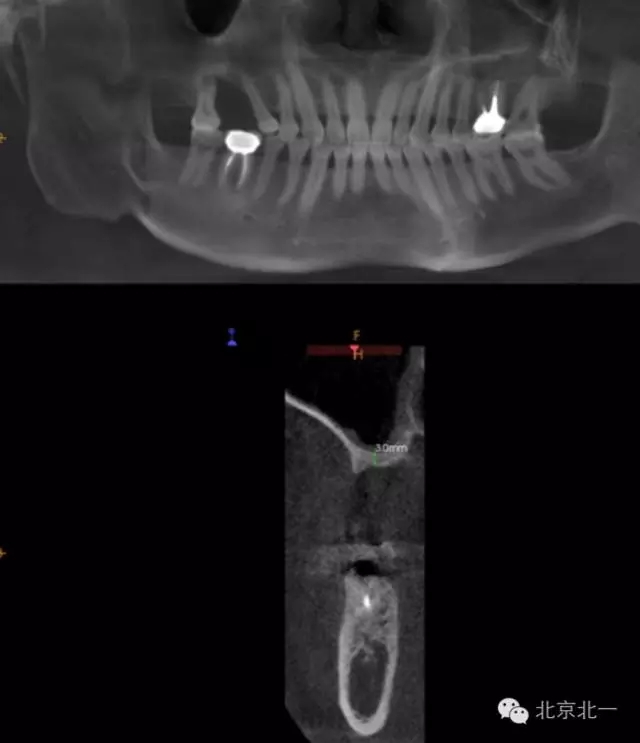

CBCT顯示,骨寬度可,骨高度不足,月3mm。頜間距離增大。

圖二:手術(shù)前全景片

圖三:骨高度3mm.

圖十八:手術(shù)前CBCT

圖十九:手術(shù)后當(dāng)天CBCT